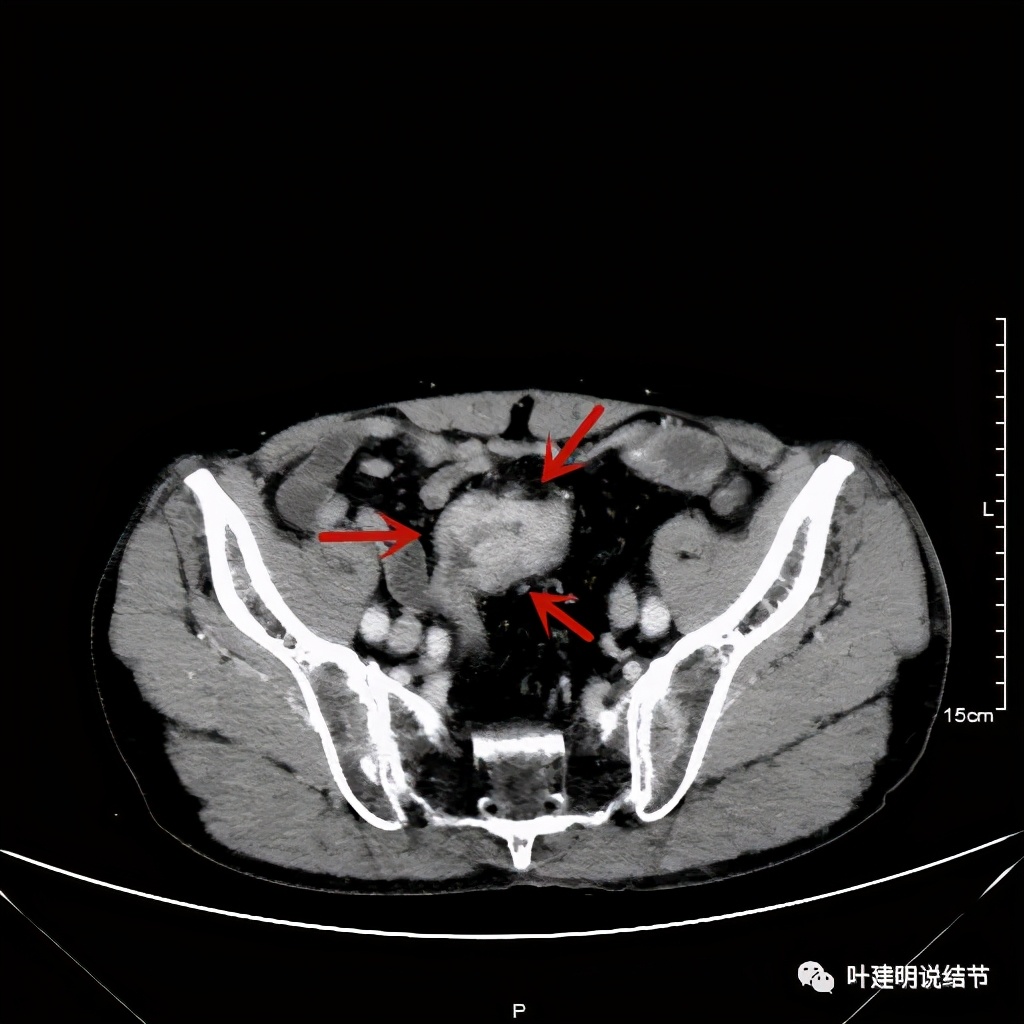

以上诸图红色示乙状结肠肿瘤,绿色示其下方正常的乙状结肠及直肠